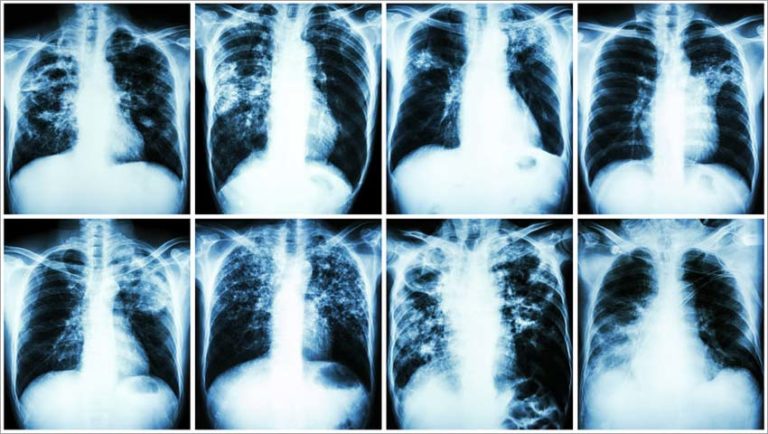

A data de 24 de março marca o Dia Mundial da Tuberculose, uma das enfermidades mais antigas do mundo, mas que ainda mata cerca de um milhão de pessoas anualmente em todo o mundo. No Brasil, cerca de 5 mil perdem a vida em razão da doença todos os anos, segundo dados do Ministério da Saúde. São índices graves, especialmente quando se trata de uma doença curável em praticamente todos os casos, desde que o tratamento seja feito corretamente.

“Assim como a tuberculose, a Covid-19 geralmente afeta os pulmões. Nas duas doenças, o paciente também pode apresentar tosse e febre. É provável que pessoas com alguma condição nos pulmões, como os pacientes com tuberculose ou com sistema imunológico debilitado, possam sofrer formas mais graves de Covid-19, se infectadas”, explica o enfermeiro, ressaltando que ainda não há dados conclusivos sobre pacientes com tuberculose infectados pelo Coronavírus.

Outros sintomas comuns em paciente com tuberculose são: tosse seca ou com secreção por mais de três semanas, cansaço excessivo, suor noturno, falta de apetite, emagrecimento acentuado e rouquidão. Há casos, no entanto, de pacientes que não exibem sinais da doença de imediato ou apresentam sintomas mais leves, o que pode confundir e retardar o diagnóstico correto.